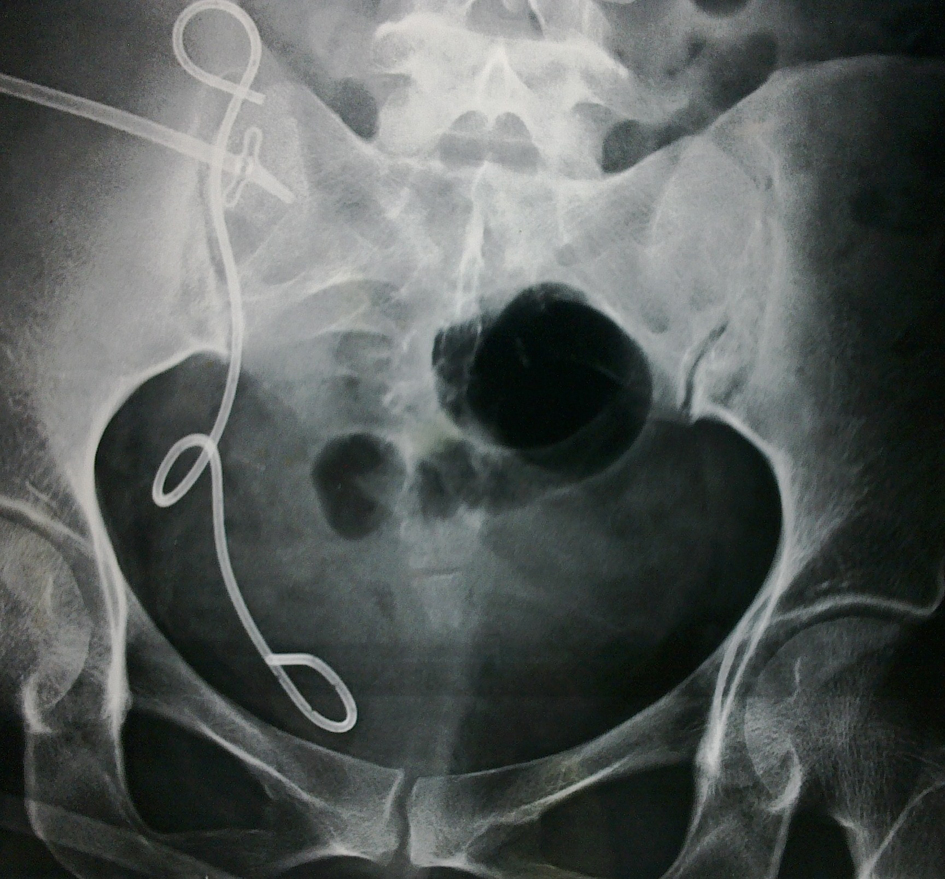

All cases of urinary leak were initially treated with prolonged catheterization. Eight out of thirteen cases responded to catheterization alone. In one out of five cases PCN (percutaneous nephrostomy) was placed even with stent in place. He did not respond to endourological management and required surgical revision which revealed terminal necrosis of ureter which required revision of anastomosis (Fig. 1, 2). Four out of five revealed leak after stent was removed which responded to PCN placement. Two patients had forgotten stent which was removed 36 and 11 months respectively. No events like stent migration, broken stent, stent related stone, hematuria or stent related obstruction was noted.

![]() Click for large image | Figure 1. PCN done for hydronephrosis of transplant kidney despite stent in place. |